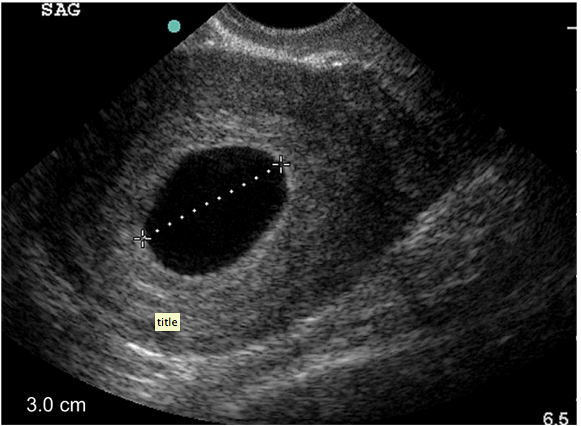

A recent issue of EP monthly also had a case by a great friend, Dr. Teresa Wu and her colleague, Dr Brady Pregerson, called Coming on Empty. They discuss a 29year old female who is pregnant and c/o cramping and vaginal spotting with the below ultrasound image. What do you do and what does it mean? What are the tips and tricks when you see the below image? They discuss it all.